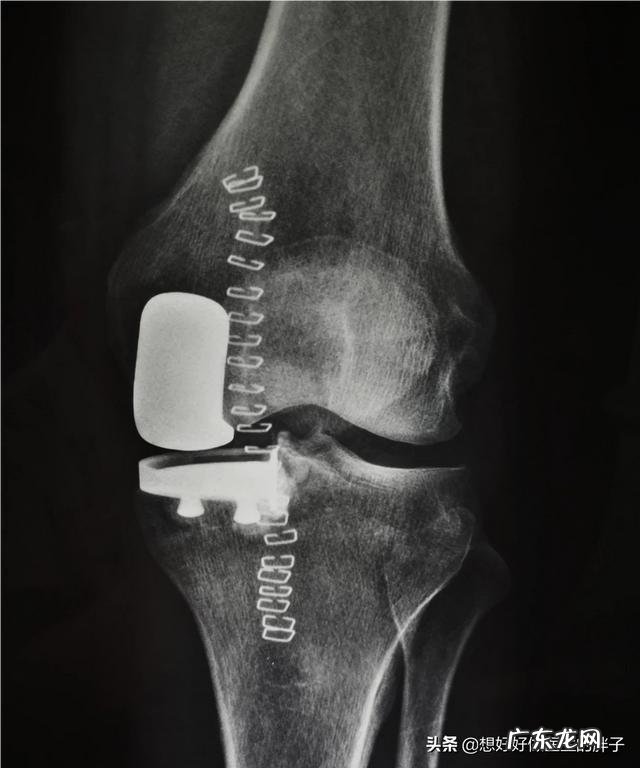

晚期的患者,通常会表现为比较严重的膝关节疼痛,有部分患者会出现明显的关节屈伸障碍,当病情严重到出现静息痛及夜间痛的时候,说明患者的病情已经达到了必须要手术才能解决的程度 。这种手术我们称之为膝关节置换手术,很多人以为是将整个膝关节的骨头切除换成假体,这种理解是错误的,膝关节的置换手术是将破损的软骨表面去掉换上一层金属的表面,所以也叫膝关节表面置换术 。而且随着目前技术的进展,为了更多的保护和保留患者的关节,现在也开始进行部分关节置换术 。

当患者经过关节置换的手术zhi疗以后,要经过良好的系统的康复锻炼,将会获得非常好的术后效果 。